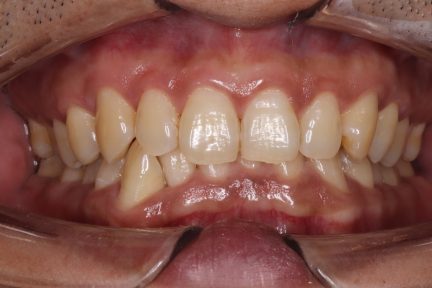

État initial

État final

Résultats obtenus

- Relation de Classe I maintenue

- Guidage fonctionnel des canines des deux côtés

- Surplomb et recouvrement normaux obtenus

- Supraclusion améliorée

- Surplomb amélioré

- Amélioration significative du surplomb

- Amélioration significative du recouvrement

- Axes médians qui coïncident

- Inclinaison axiale correcte des incisives

- Courbe de Spee nivelée

- Arcades alignées et coordonnées

- Alignement des deux arcades par le biais d'une dérotation

- Forme d'arcade améliorée

- Ligne esthétique du sourire obtenue

- Cas où tous les objectifs de traitement ont été atteints

- Arcades harmonieuses obtenues